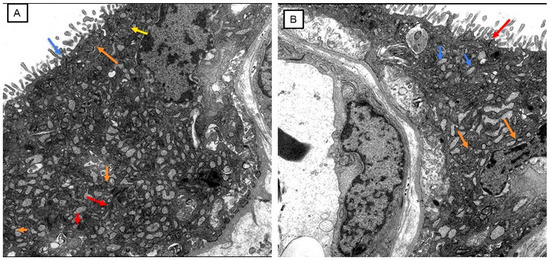

Placental Autophagy Modulation and Ultrastructural Changes in COVID-19 Patients: A Pilot Study Using Immunohistochemistry and Transmission Electron Microscopy

Background: Autophagy is a conserved intracellular degradation pathway essential for maintaining cellular homeostasis by recycling damaged organelles and proteins. Dysregulation of autophagy has been implicated in pregnancy-related complications such as preeclampsia and fetal growth restriction, underscoring its importance in maternal and fetal health. However, the autophagy status in the placental tissue of COVID-19-infected pregnant women remains unknown. Objective: To investigate autophagy activity in term placentas from pregnant women infected with COVID-19 compared to those from uninfected control pregnant women. Methods: In this prospective cross-sectional single-center study, 15 COVID-19-positive and 15 COVID-19-negative term pregnant women who delivered at Sultan Qaboos University Hospital between January 2020 and December 2022 were included. Immediately after delivery, the placental tissue samples were collected and assessed for autophagy activity using immunohistochemistry for LC3B and p62 markers, histopathological examination, and transmission electron microscopy. The proportion and intensity of LC3B and p62 staining were quantified. Statistical analysis was performed using the Mann–Whitney U test. Results: There was a significant reduction in p62 and LC3B expression in both the proportion and intensity in COVID-19 placentas compared to the control group. The proportion of p62 (p = 0.001) and LC3B (U = 46.000, p = 0.003) was significantly reduced in infected placentas. Similarly, intensity levels of both markers showed significant differences (p < 0.05), supporting the evidence of reduced LC3B/p62, suggesting autophagy modulation in COVID-19 patients’ placentas. Additionally, abnormal ultrastructural changes were observed in COVID-19–positive placentas, including mitochondrial injury, endoplasmic reticulum stress, microvillus loss, and basement membrane thickening. Conclusion: The study results from a limited sample size demonstrate a significantly altered autophagy flux in the placental tissues of term pregnant women with COVID-19 infection. These findings highlight the potential impact of COVID-19 infection on placental function and fetal development and underscore the need for further investigation into autophagy-modulating strategies to improve maternal–fetal health. Full article